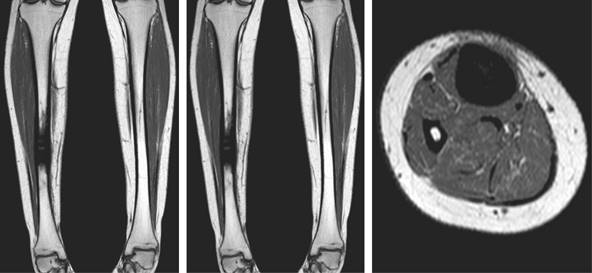

Se realizaron radiografías que demostraron una lesión intraósea diafisiaria única, de localización central, con bordes definidos, periostio engrosado pero sin interrupción y sin signos de malignidad. No se observó afectación de los tejidos blandos ni destrucción ósea adyacente (Figura 1). La resonancia magnética confirmó los hallazgos descritos; la lesión se caracterizó como inespecífica, con apariencia esclerosa y ocupación de toda la cavidad medular, con engrosamiento de ambas corticales (Figura 2). Se realizó una gammagrafía ósea que demostró una posible reacción osteogénica avanzada con evidencia de patología inflamatoria secundaria a destrucción ósea. Se realizó una biopsia incisional cerrada, que descartó lesiones infecciosas o neoplásicas.

Figura 2: Cortes coronales y sagitales de la resonancia magnética en los que se muestra lesión homogénea intraósea en tibia derecha.